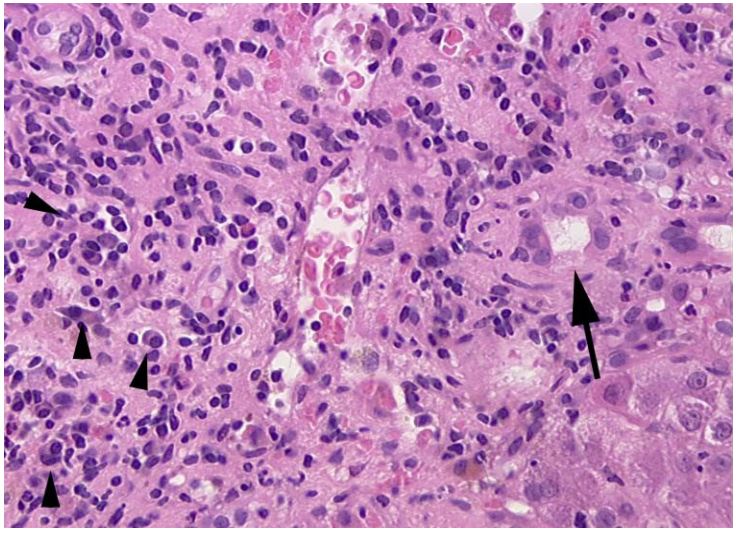

Figure 1: Patient n°1: enlarged portal tract infiltrates with numerous plasma cells (arrow head) and eosinophils, surrounding a damaged bile duct (arrow).

Figure 2: Moderate portal inflammation mainly constituted of eosinophils; bile duct (arrow) was destroyed by the infiltrate and canalicular cholestasis was marked (arrow head).